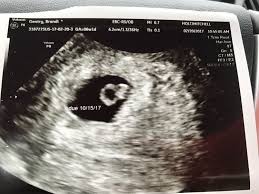

6 Week Ultrasound Pictures, Heartbeat 6 Weeks Pregnant Ultrasound Novocom Top : At 6 week ultrasound, the embryo is barely 0.25 inches, which is the size of a sweet pea.. 6 week 3d ultrasound pictures pregnancy baby images 4d. Transabdominal ultrasound will provide a panoramic view of the abdomen and pelvis and is noninvasive, whereas transvaginal ultrasound provides a more limited pelvic view and requires insertion of a probe into the vagina. What does it mean if there's no yolk sac at 6 weeks? The circle there is the yolk sac. Diagnostic ultrasound in the first trimester of pregnancy glowm.

Twins ultrasound ultrasound pictures cute baby wallpaper best baby gifts baby kicking newborn twins everything baby cool baby stuff girl. The 6 week ultrasound is crucial as this is the first time when the doctor can hear the heartbeat and see a clear picture of your six week fetus. Here are reasons for an ultrasound during week 6 of pregnancy. Ultrasound examination establishing the gestational age of the. 6 week ultrasound pictures at this gestation, what the ultrasound. Having a 6 week ultrasound? Ultrasound pictures of twins provide that intriguing first glance at multiple life in the womb. 6 week ultrasound twins' pictures.

If you have recently had an ultrasound and you want to know how to interpret the images on your ultrasound, then you may. Sorry the 6 week update is so late! 7 weeks 6 days ultrasound w heartbeat youtube. Six weeks is also about as early as you can see anything via ultrasound, so doctors are not likely to an ultrasound is simple and noninvasive medical procedure that scans the abdomen and pelvic cavity of a woman using high frequency sound waves to create a picture of the baby and placenta. Here, learn what to expect and whether 3d and 4d scans are safe. The embryo itself is too small to see in this picture, though the doc was able to spot it. Here are reasons for an ultrasound during week 6 of pregnancy. Ultrasound pictures at 6 weeks 1 day. 6 weeks ultrasound twinspictures will also confirm that you are. Details on 6th week pregnancy symptoms & baby development >>. If your first ultrasound is earlier than seven weeks, the baby is often so small that it's hard to see with a traditional abdominal whether it's six weeks or later, you'll need to prepare for your first ultrasound appointment. Fetal yoke sac as seen on ultrasound at eight weeks. 6 week ultrasound | ivf journey 2018.

Here are reasons for an ultrasound during week 6 of pregnancy. Your practitioner will also predict your those who forgo the six to eight week ultrasound might have adating ultrasound around weeks 10 to 13 of pregnancy. Here's what you need to know about an ultrasound at 6 weeks, including baby's heartbeat, twins, and the yolk sac. Having a 6 week ultrasound? The doctor also heard a heartbeat.

Picture of ultrasound at 5 to 6 weeks of pregnancy. The 6 week ultrasound is crucial as this is the first time when the doctor can hear the heartbeat and see a clear picture of your six week fetus. 6 weeks ultrasound twinspictures will also confirm that you are. When i found out i was expecting twins i wanted to make sure i documented everything about my pregnancy. Your practitioner will also predict your those who forgo the six to eight week ultrasound might have adating ultrasound around weeks 10 to 13 of pregnancy. It shows my uterus, the dark shape in the middle. #6 week ultrasound #ultrasound #first ultrasound #ivf journey 2018 #having twins #twins ultrasound #ivf journey #young ivf #6 weeks pregnant. At six weeks' gestation, it's possible to see the baby's heartbeat. Check out hundreds of amazing twin ultrasound images! Ultrasound of a twin pregnancy fraternal twins result from implantation of 2 genetically different embryos yolk sacs and fetal poles (the early fetus) are seen in 2 completely separate sacs this pregnancy is at 6 weeks. At 6 week ultrasound, the embryo is barely 0.25 inches, which is the size of a sweet pea. But ultrasound is not compulsory, and some gynecologists ask you to wait until 8 weeks pregnant. An ultrasound with twins will show the babies as two dark spots in the uterus.